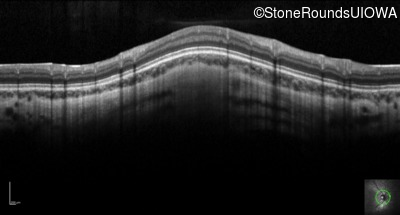

Optical Coherence Tomography - Right - 20/80 +2

Exemplar / OCT Stack